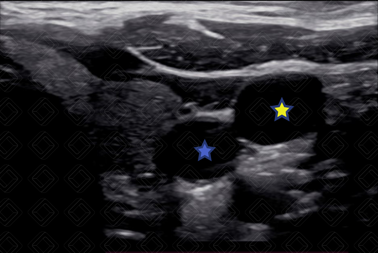

4. USG pré-procedimento para visualização anatômica e planejamento (Figura 2).

Texto alternativo para a imagem Figura 2. USG pré-procedimento evidenciando carótida comum direita (estrela azul) e veia jugular interna direita (estrela amarela). Créditos: Dr. Igor Biscotto - Rio de Janeiro/RJ.